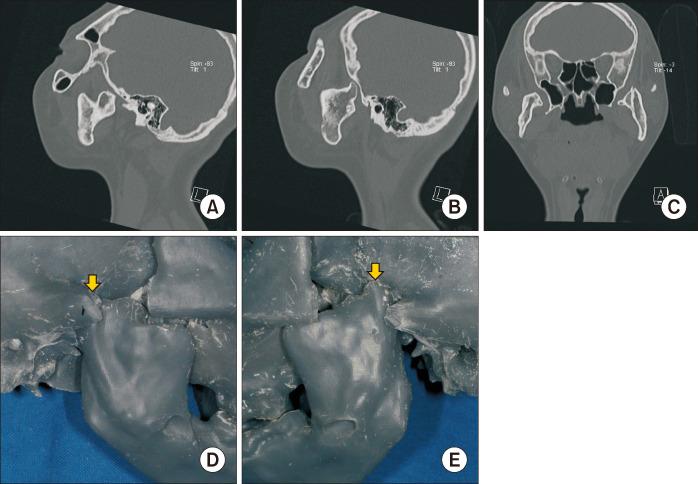

Untreated mandibular condyle fractures in childhood can result in significant jaw deformities, such as mandibular retrognathism, open bite, and facial asymmetry, which may necessitate surgical intervention in later years. Surgical approaches vary depending on the severity of the condition, including mandibular surgery alone, maxillomandibular surgery, or mandibular distraction osteogenesis (MDO). This report highlights a case involving mandibular retrognathism and open bite with condylar dislocation and malunion caused by untreated pediatric condyle fractures. Key challenges in this case included excessive anterior mandibular movement, irregular morphology of the mandibular ramus caused by malunion from fracture healing, and anteromedial dislocation of both condyles, all of which posed significant surgical complexities. The surgical approach combined Le Fort I osteotomy with MDO to perform maxillary impaction and mandibular advancement, followed by a secondary genioplasty. Notably, the dislocated temporomandibular joints were left untreated. Two years postoperatively, no relapse or recurrence of open bite was observed, and the dislocated condyles showed no positional and morphological changes, reflecting favorable outcomes. To our knowledge, this is the first reported case of orthognathic surgery combined with MDO for bilateral dislocated mandibular condyles, making it a valuable contribution to clinical practice.

儿童期未经治疗的下颌髁突骨折可导致严重的颌骨畸形,如下颌后缩、开颌和面部不对称,这可能在日后需要手术干预。手术方法因病情严重程度而异,包括单纯下颌手术、上颌下颌联合手术或下颌骨牵张成骨术(MDO)。本报告重点介绍了一例因儿童期髁突骨折未经治疗导致下颌后缩、开颌伴髁突脱位和骨不连的病例。该病例的主要挑战包括下颌前部过度移动、骨折愈合导致的骨不连引起的下颌升支形态不规则以及双侧髁突向前内侧脱位,所有这些都带来了重大的手术复杂性。手术方法结合了Le Fort I截骨术和MDO,以进行上颌骨上移和下颌骨前徙,随后进行二期颏成形术。值得注意的是,脱位的颞下颌关节未进行治疗。术后两年,未观察到开颌复发或再发,脱位的髁突也未出现位置和形态变化,显示出良好的效果。据我们所知,这是首例报道的正颌手术联合MDO治疗双侧脱位下颌髁突的病例,对临床实践具有重要价值。